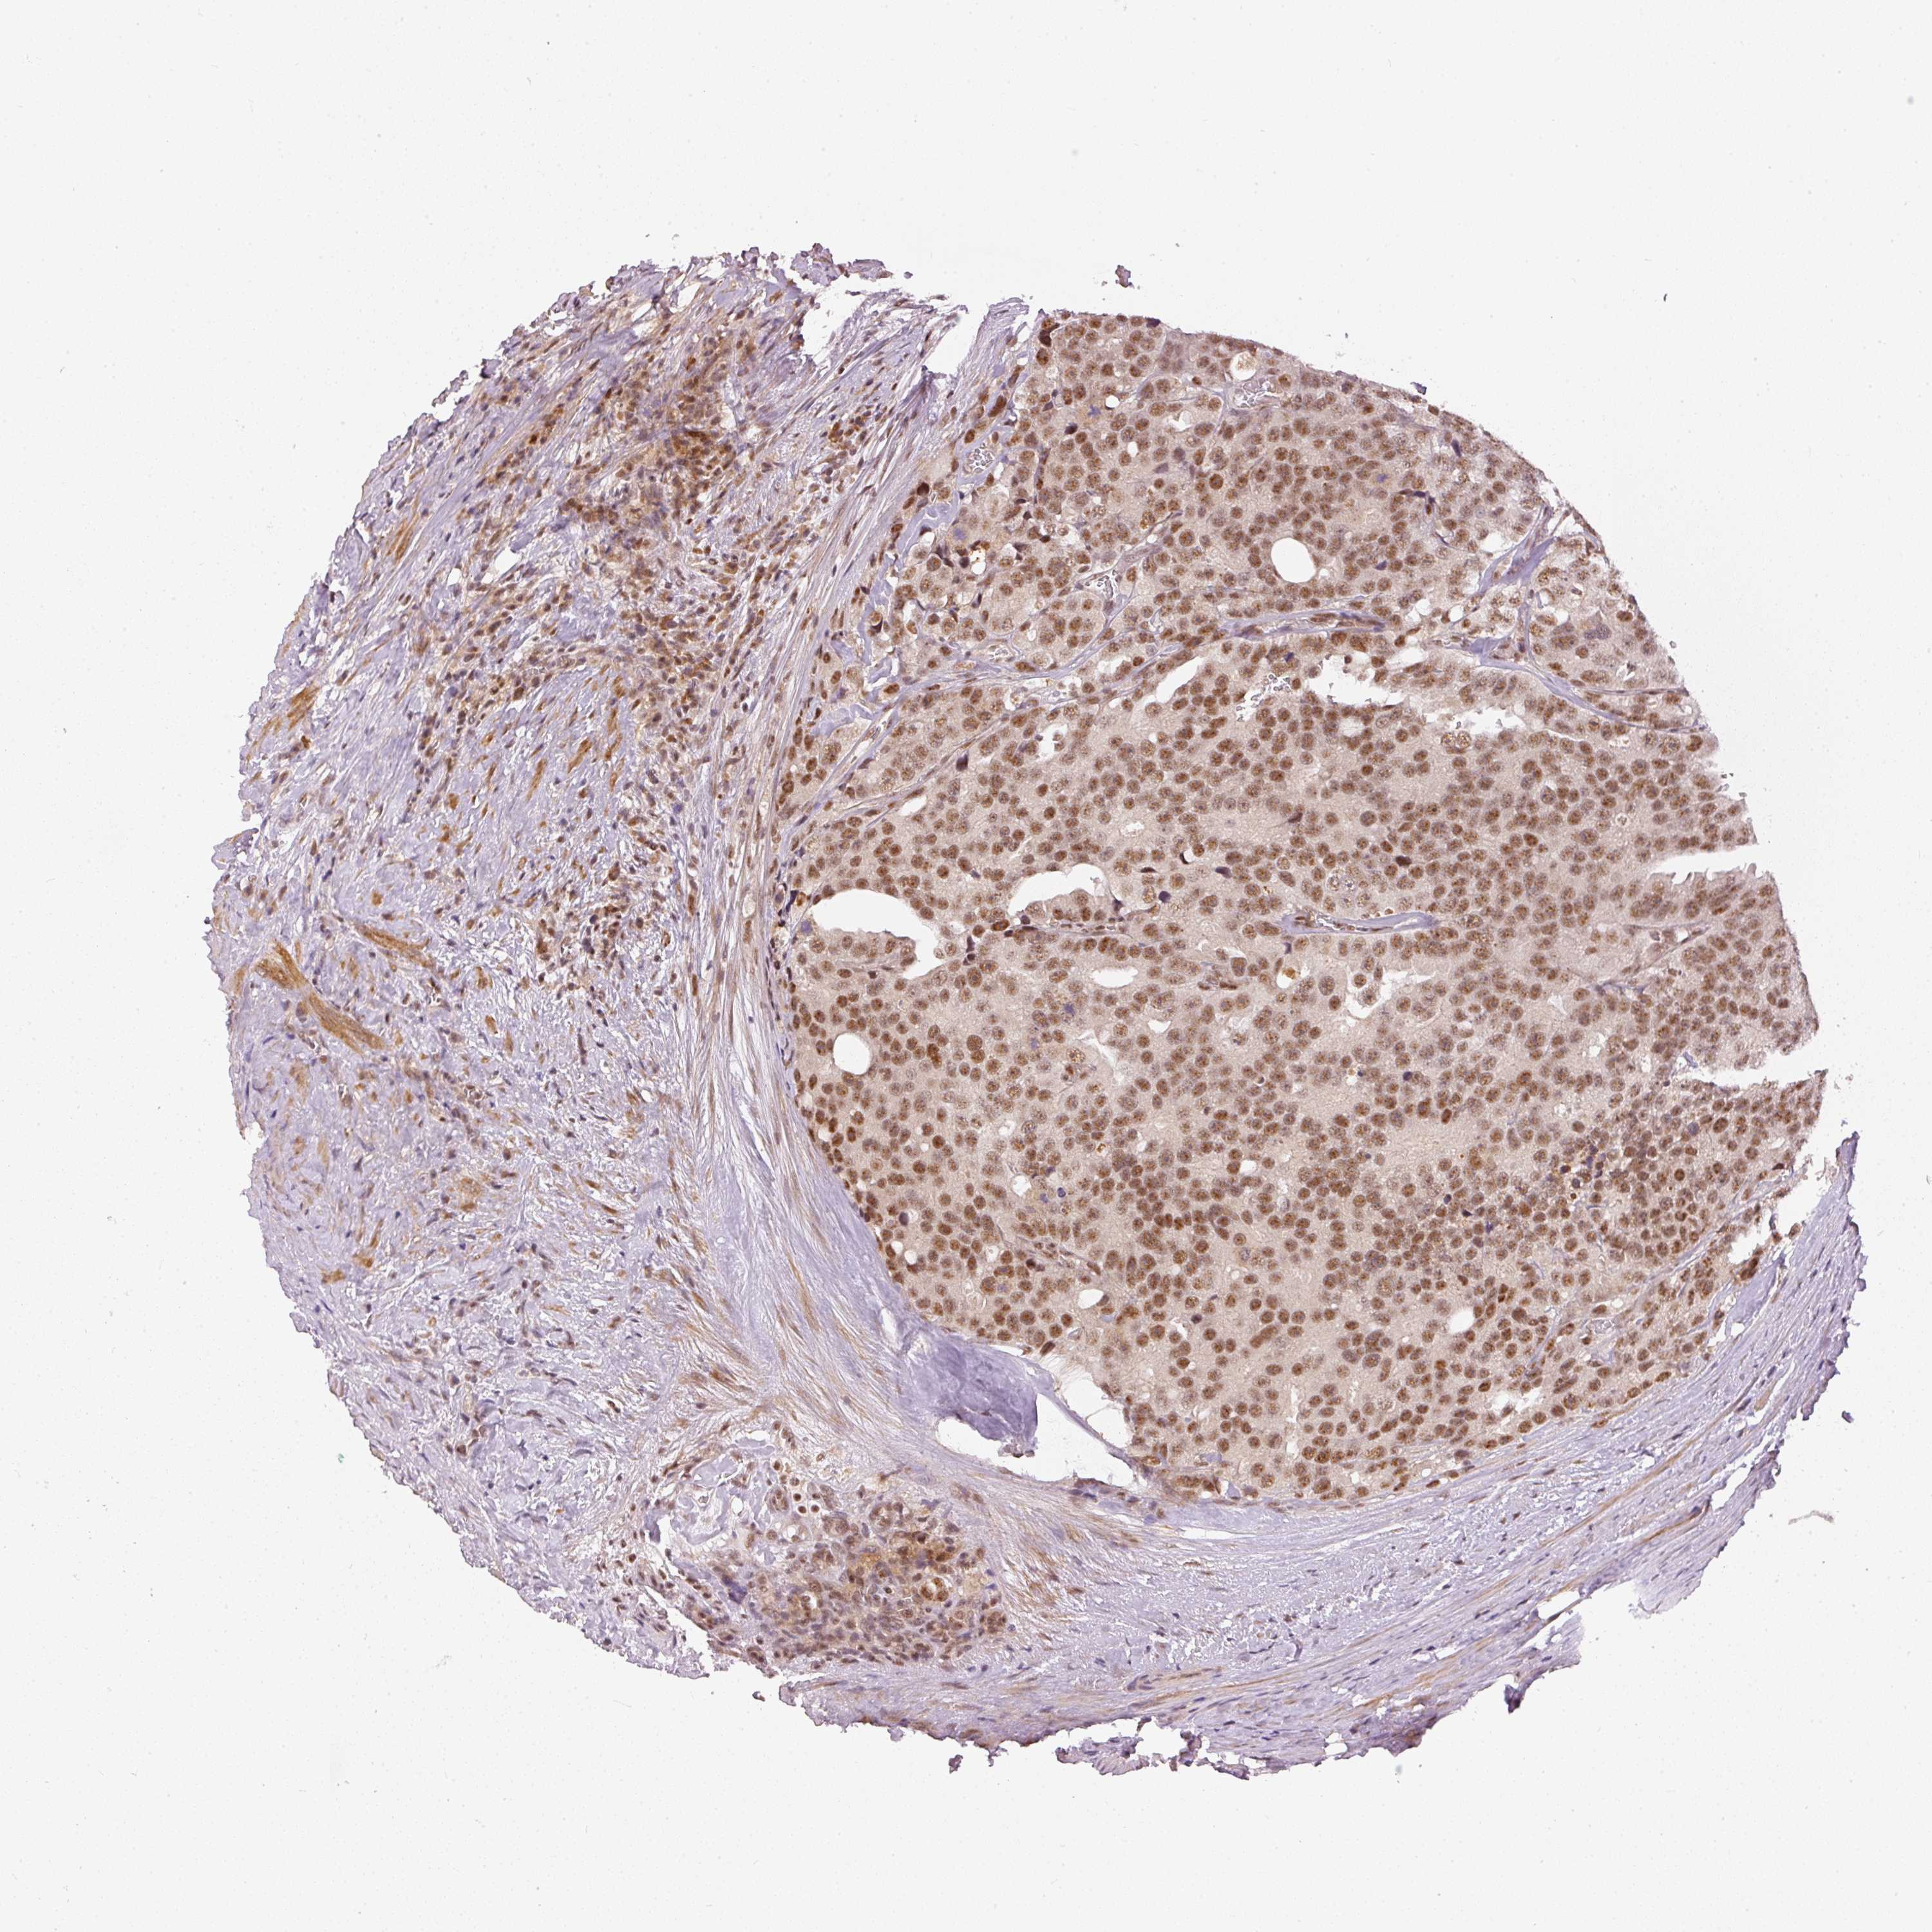

PROSTATE CANCER - Protein expressioni

A mouse-over function shows sample information and annotation data. Click on an image to view it in a full screen mode. Samples can be filtered based on level of antibody staining by selecting one or several of the following categories: high, medium, low and not detected. The assay and annotation is described here.

Note that samples used for immunohistochemistry by the Human Protein Atlas do not correspond to samples in the TCGA dataset.

Antibody stainingi

Antibody staining in the annotated cell types in the current human tissue is reported as not detected, low, medium, or high, based on conventional immunohistochemistry profiling in selected tissues. This score is based on the combination of the staining intensity and fraction of stained cells.

Each image is clickable and will lead to virtual microscopy that enables deeper exploration of all samples and also displays staining intensity scores, fraction scores and subcellular localization as well as patient and tissue information for each sample.

Antibody HPA052953

Staining

High

Medium

Low

Not detected

Intensity

Strong

Moderate

Weak

Negative

Quantity

>75%

75%-25%

<25%

None

Location

Nuclear

Cytoplasmic/membranous

Cytoplasmic/membranous,nuclear

Adenocarcinoma, NOS

Adenocarcinoma, High grade

Adenocarcinoma, Low grade